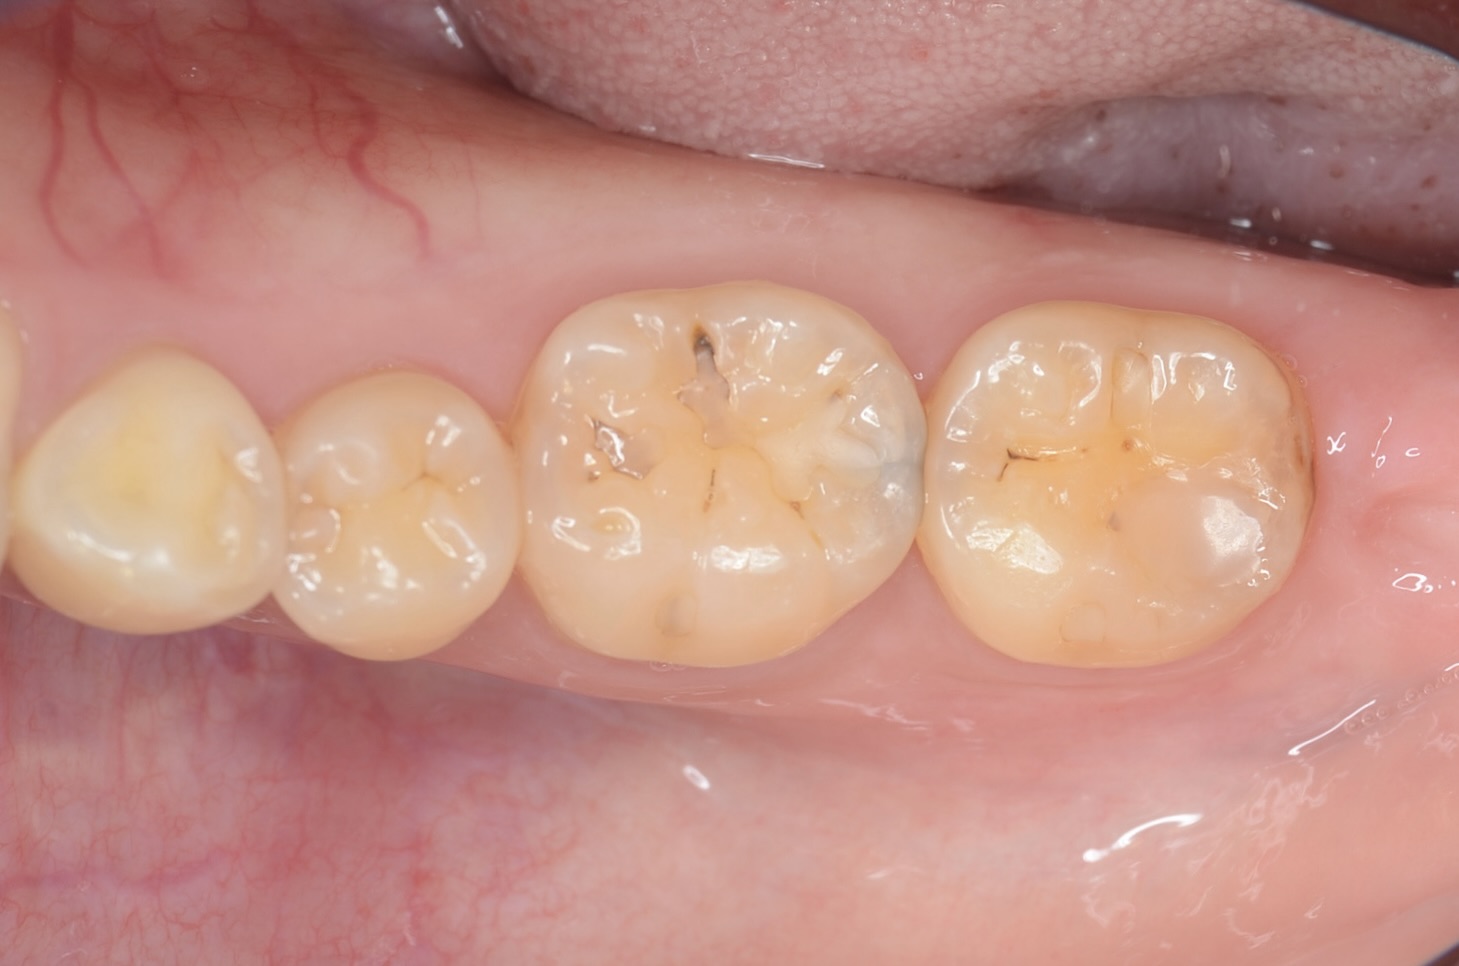

After

7番近心面の虫歯

7番近心に虫歯があります。 齲蝕検知液で青く染まります。 -

虫歯を削っていきます。 -